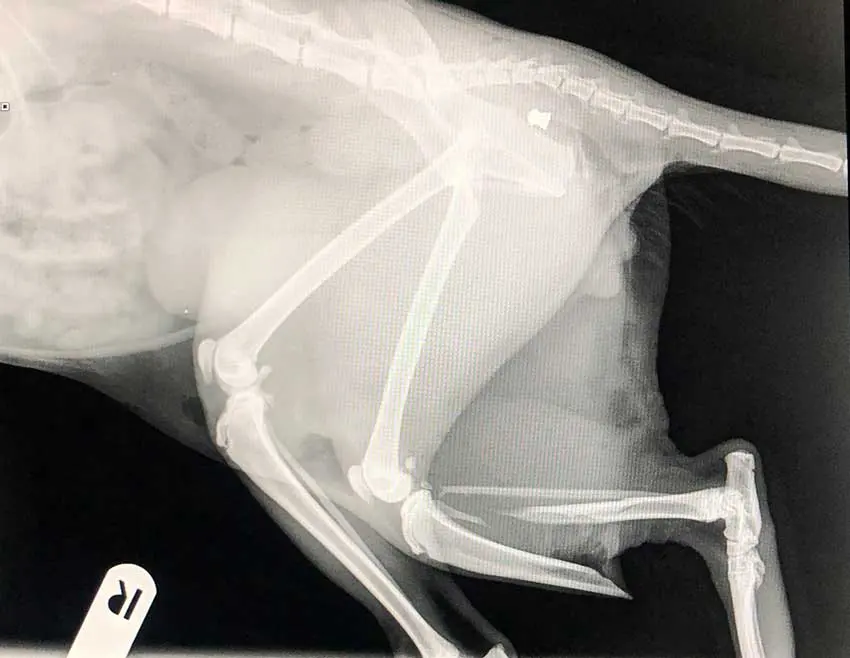

Radiographs can identify injuries or disease processes within the body by visualising bones, organs and other soft tissue structures – anything from fractures and osteosarcomas to bladder stones, foreign bodies and gastric dilation volvulus.

As a part of every veterinary nurse’s training journey, they must complete a diagnostic imaging module that includes tasks such as setting up x-rays, positioning patients for x-rays and processing x-rays. With this training and the anaesthetic training taken into consideration, no reason exists why nurses are not able to lead x-ray cases when these come into practice, with the veterinary surgeon using these images to diagnose and create a treatment plan.